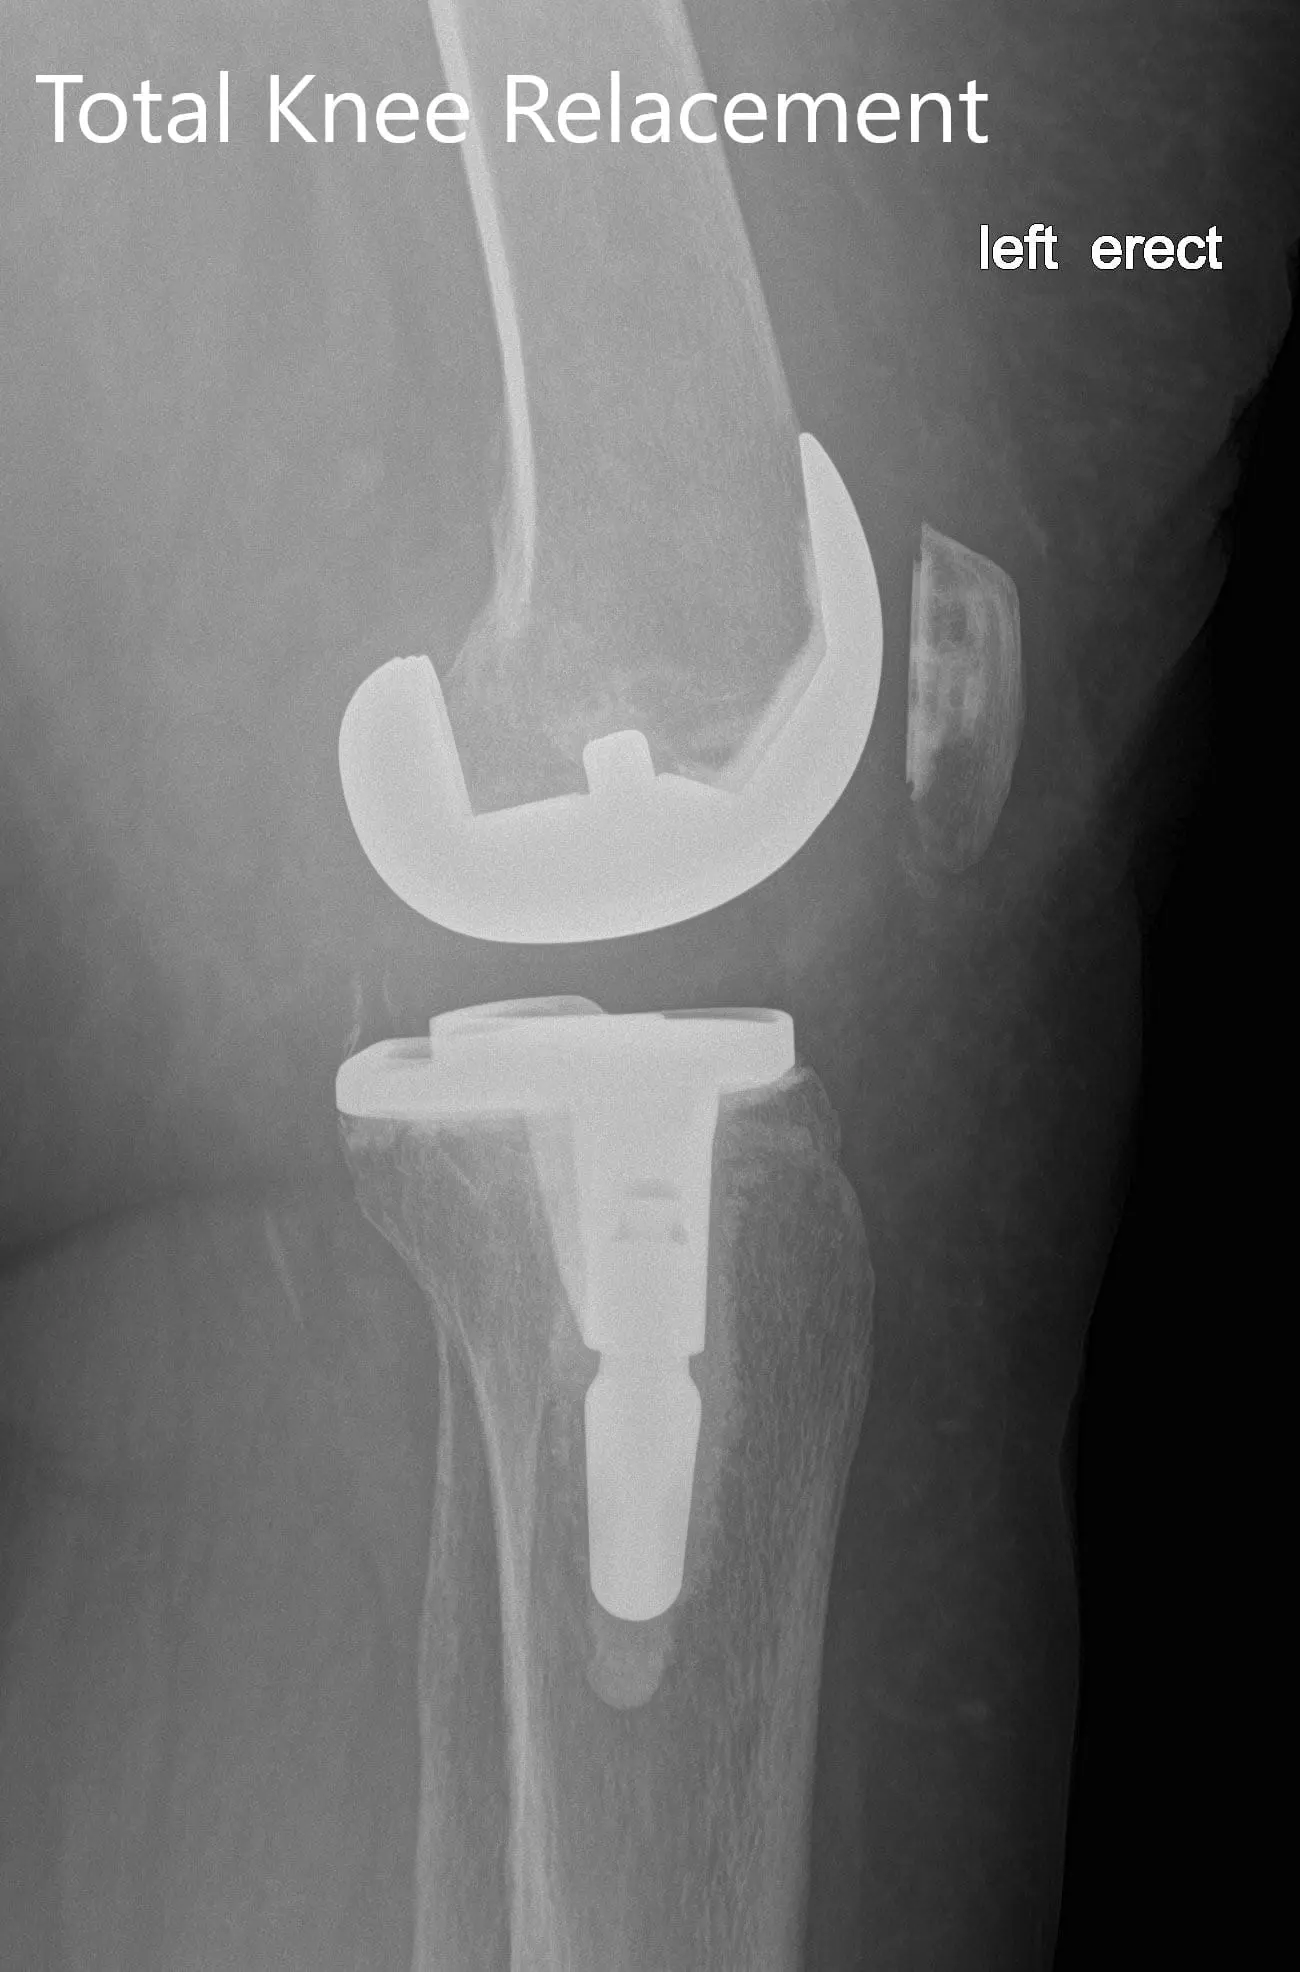

Postoperative X-ray of the left showing the anteroposterior and lateral view with total knee prosthesis in position

IMPLANTS USED: Posterior stabilized 8 left standard femoral component left-sided with tibia E left cemented with 14 x 30 stem with poly 16 mm with a 29-mm diameter poly patella.